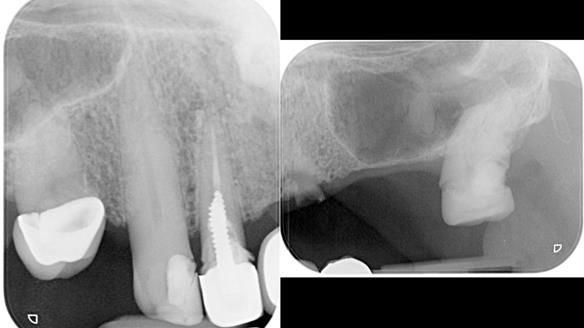

This edition features the case of Edgar, who sought help for a poorly fitting, acrylic-based partial denture that rocked, affected his speech, and caused discomfort. After considering various treatment options, including dental implants, Edgar opted for a metal-based removable partial denture, designed by myself with input from my technician, Rowan Garstang.

Treatment Process: I provided the clinical work while Rowan Garstang delivered the technical aspects. The treatment required fifteen visits to fit and review Edgar.